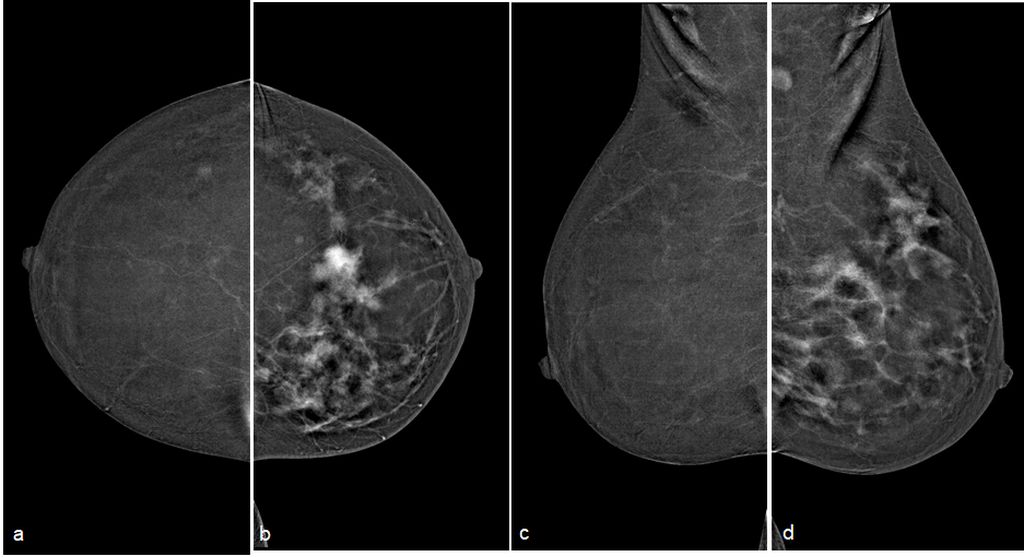

Low energy 2D mammogram images of both breasts in CC and MLO views (figure 1) demonstrate focal asymmetry with architectural distortion in the upper central quadrant of the middle third in the left breast with associated architectural distortion. Fine pleomorphic calcifications in regional distribution are noted in the inner central and upper inner quadrants of the left breast (figure 2). Diffuse skin and trabecular thickening is noted in the left breast. On post contrast recombined images (Figure 3), the area of focal asymmetry shows a heterogeneously enhancing mass with washout on delayed image (MLO). Heterogeneous and clumped non-mass enhancement in diffuse distribution is noted involving the areas of calcifications in the inner quadrant (red circle in figure 4) which could represent calcified ductal carcinoma in situ (DCIS) as well in the outer quadrant (green circle in figure 4) which could represent non-calcified DCIS. To differentiate between non-mass enhancement in diffuse distribution and background parenchymal enhancement, comparison with the opposite breast should be done. In our case there is minimal background parenchymal enhancement in the right breast (figure 3a and 3c) whereas clumped enhancement in diffuse distribution in the left breast (figure 3b and 3d) suggestive of non-mass enhancement in the left breast. Ultrasound correlation revealed an irregular isoechoic mass with indistinct margins with no posterior features measuring 2.2x1.9x1.6cm at 11:30 O'clock position, 6cm fn in left breast. It is hard on elastography (Figure 5). Non-mass ductal abnormalities in the form of irregular prominent and dilated ducts filled with soft tissue and echogenic foci within are noted in upper inner, lower inner and upper outer quadrants of left breast (Figure 6). The whole abnormality extends from the 8-12-3 o'clock position of the left breast. On tomo slices two equal density lesions with indistinct margins are noted in the upper outer quadrant of the right breast. On post contrast recombined images, they show heterogeneous enhancement. Ultrasound correlation revealed two hypoechoic lesions with circumscribed margins in the upper outer quadrant. Multiple enlarged left level I and level II lymph nodes are noted, which show asymmetrical cortical thickening and loss of fatty hilum (figure 7). MRI post contrast subtraction axial images (figure 8a and b) revealed a lesion with irregular shape and margins in the upper central quadrant of left breast with associated non-mass enhancement in diffuse distribution in upper inner, upper outer and lower inner quadrants confirming the mammographic extent of abnormalities (figure 8c).